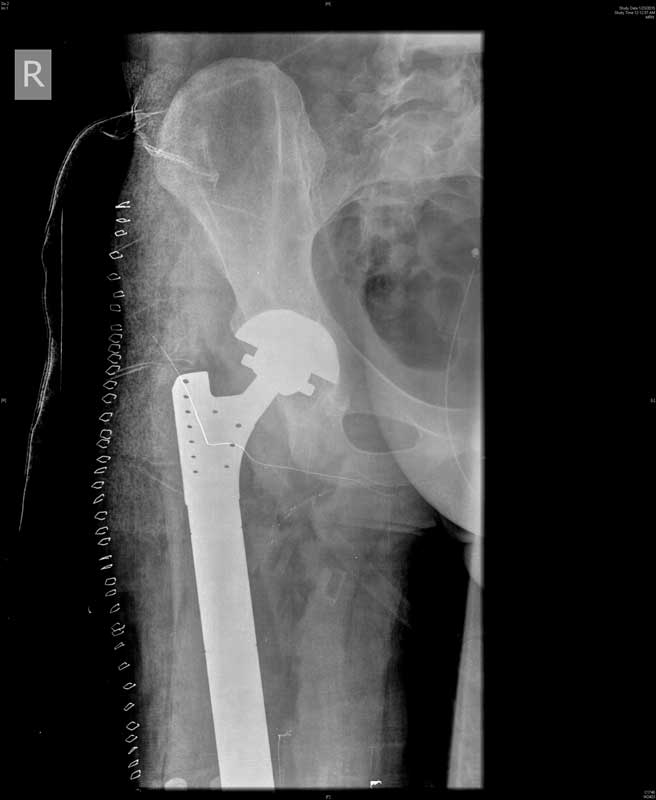

It is in New Delhi that the young Uzbek man got much needed medical succor. In a rare and difficult surgery that lasted 8 hours, Dr Rajeev K Sharma, Senior Consultant, Orthopedics & Joint Replacement Surgeon along with his team including Dr. V.P Singh, Cancer Surgeon at Indraprastha Apollo Hospitals, New Delhi, removed the entire cancer-affected bone right from the hip to the knee, replacing it with an artificial Total Femoral Replacement implant.

The difficult surgery which was a combination of Hip & Knee Replacement has successfully cured the patient of cancer, eliminating the risk of a permanent disability. A failure to get rid of the cancer affected bone would have lead to two eventualities: either a disarticulation of the hip (surgical removal of the entire lower limb at the hip level) or an amputation of the leg to save the life of the man. However, both these situations would have resulted in permanent disability.

“Total Femoral Replacement in this case was a very difficult and rare surgery as it was a kind of a combination of hip replacement, knee replacement and thigh bone replacement. To be able to get rid of the cancer completely, we needed to remove the entire stretch of thigh bone from the right hip to the right knee and reconstruct the same artificially. It was a challenging surgery as it involved the removal of whole thigh bone at the same time. The challenges included threat of post-surgical infection, knee and hip instability and damage to the nerves and vessels of the area. However, in an 8-hour procedure we successfully removed the full cancerous thigh bone and replaced it with an artificial Total Femoral Implant,” added Dr Sharma.